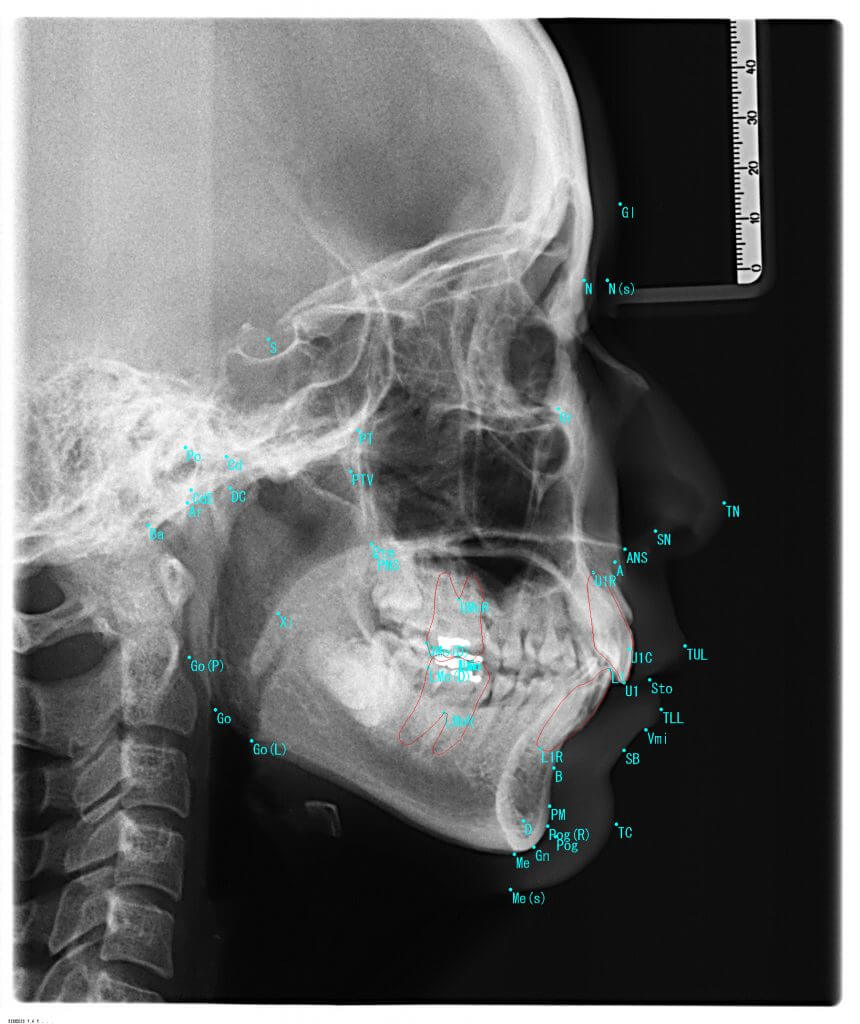

矯正診断LAS分析

矯正歯科・噛み合わせ治療